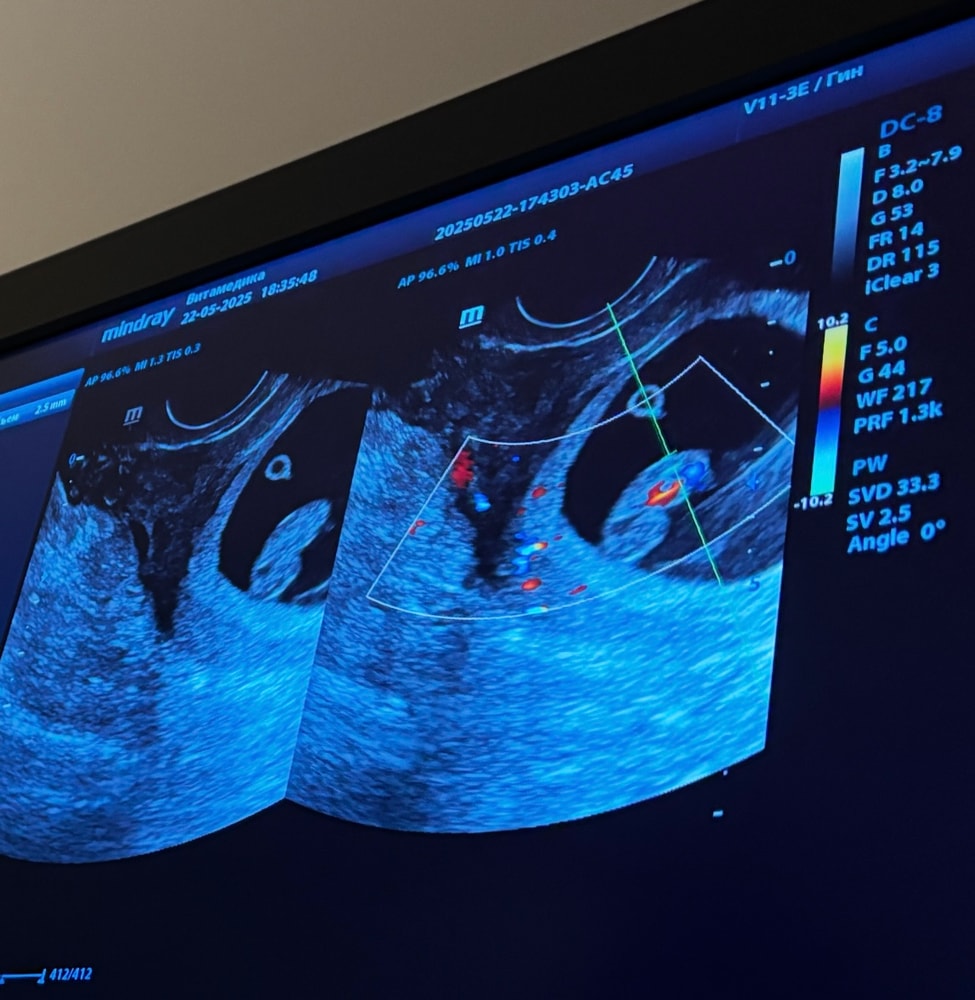

Ирина Лапина, у меня вот так сейчас 8 недель.4 дня по узи 😁 но я в это тоже не верю ,так ,погадать от делать нечего Изображение

Татьяна, я вот вообще ничего не понимаю по этим узи ,выше скинула фото

Леся Леся, по вашему узи по этому методу парень обещается

Диана, а по моему узи по итогу кто ?😁 Да ,там по Хориону определяют ,но я все ровно не понимаю особо 😁